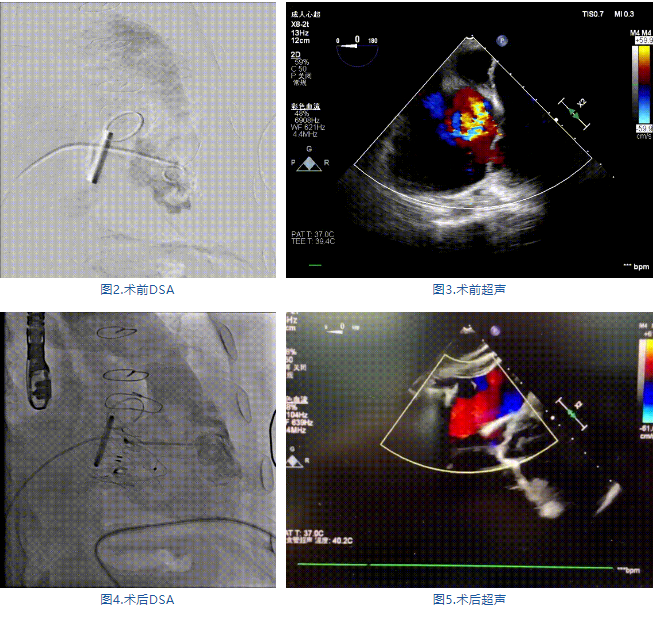

手術(shù)在全麻狀態(tài)下進行,郭惠明教授團隊采用經(jīng)右側(cè)頸靜脈入路的方式送入輸送器進入體內(nèi),并在TEE和DSA的指引下進行。在輸送器進入右室后釋放室間隔錨定裝置,旋轉(zhuǎn)輸送器,使得錨定裝置對準室間隔面;而后釋放前瓣夾持件,確定夾持件位于右室側(cè)釋放LuX-Valve Plus人工瓣膜盤片,再使用DSA和超聲確認盤片是否位于右房側(cè),同時調(diào)整瓣膜的同軸性。緊接著在DSA和超聲的監(jiān)視下調(diào)整室間隔錨定件貼合室間隔,釋放室間隔錨定裝置。再次確認瓣膜的穩(wěn)定性和同軸性后,將輸送器撤出體內(nèi),最終完成LuX-Valve Plus人工瓣膜植入(圖2-5),手術(shù)獲得圓滿成功?;颊咴谑中g(shù)室即刻拔除氣管插管,術(shù)后超聲提示LuX-Valve Plus人工三尖瓣瓣膜同軸性良好,瓣架固定牢靠,無反流和瓣周漏。